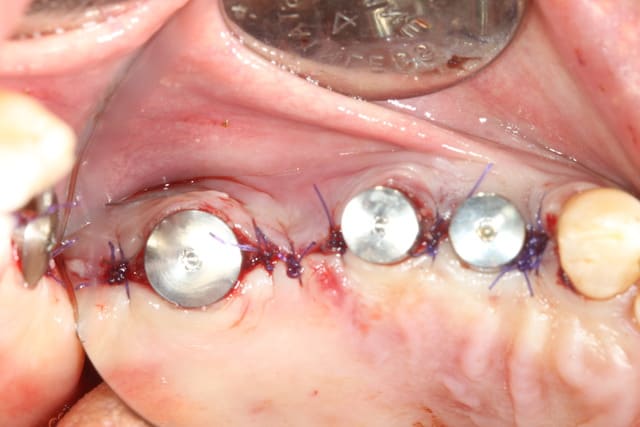

voici mon premier cas d'Extraction implantation Immediate...

ah si, juste une petite remarque (oh pas grand chose...) pour tes points de sutures...si tu veux que les berges s'affrontent bien sans bailler, fais des points plus puissants type matelassier ou en X de part et d'autre de tes vis de cicat...;-)

bien sur toute la ligne! sauf positionnement de 24 en palatin

bof, allez, peut être de 0.5mm trop palatin...pas toujours évident à faire quand l'alvéole "aspire" naturellement les forets...

amha çà va pas changer grand chose pour la prothèse...et puis au moins il n'aura pas le risque de corticale vestibulaire trop fine...

En examinant la paroi vestibulaire de l’alvéole après extraction...j'ai pensé que la résorption faisant l'option implantaire serait plus compliquée par la suite. J'ai donc posé l'implant en 24;

A posteriori je me dit que j'aurai du poser la membrane autour de l'implant pour éviter la compétition cellulaire et optimiser mon comblement.

Ici, pas besoins de membrane car ton défaut osseux est à 4 parois